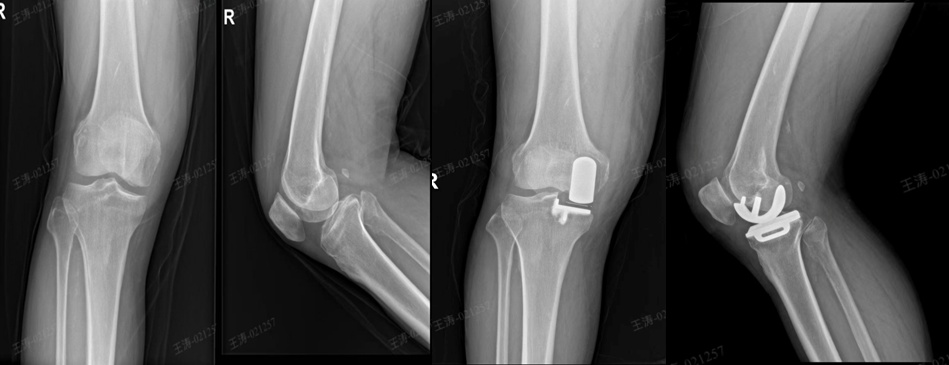

胫骨高位截骨术为“O”型腿重塑力学平衡。这项治疗主要适用于因膝内翻(“O”型腿)导致膝关节内侧过度负重、软骨磨损,但外侧间室健康的较年轻、活动量大的患者,也适用于内侧半月板后根损伤的病人。技术精髓在于通过精确截骨调整小腿力线,如同为倾斜的房屋加固地基、纠正承重轴。核心优势在于保留全部自身关节,手术不切除任何关节结构,旨在通过力线矫正,从根本上缓解关节磨损进程。这为活跃的年轻患者争取更长的“原装关节”使用寿命,是真正意义上的“预防性”修复。

胫骨高位截骨术(HTO)